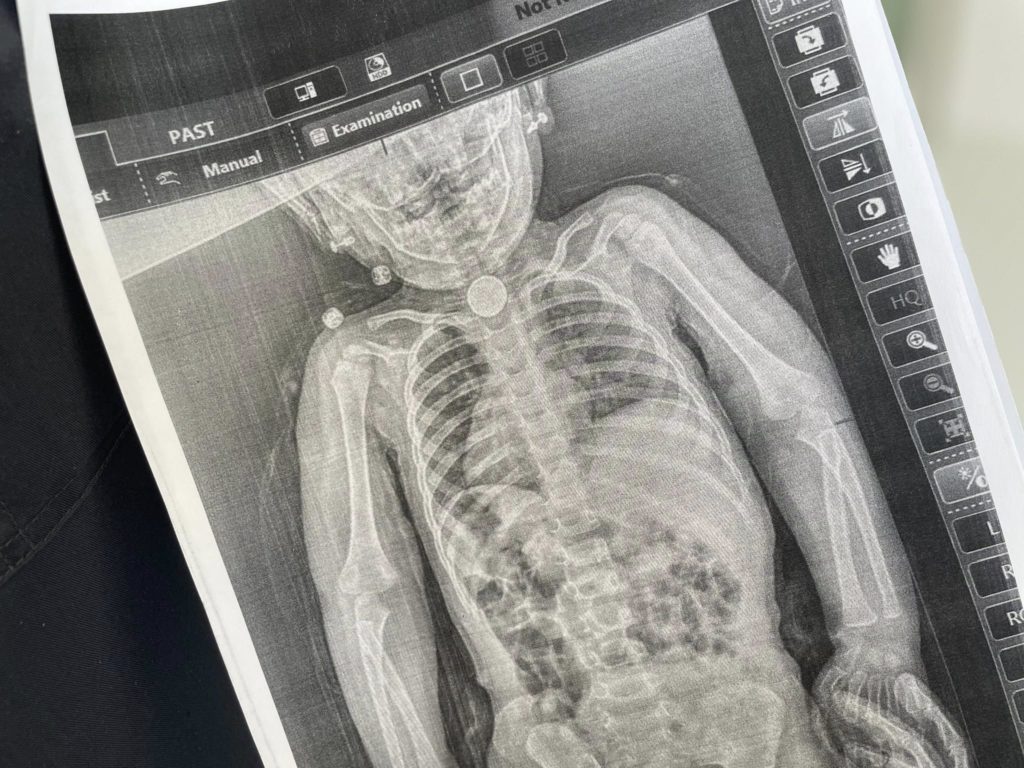

Рентген чітко показав сторонній предмет у стравоході. Під час ендоскопії лікарі встановили: у ділянці першого фізіологічного звуження застрягла батарейка. Навколо неї вже сформувалися набряк й ураження слизової — ознаки тривалого пошкодження тканин.